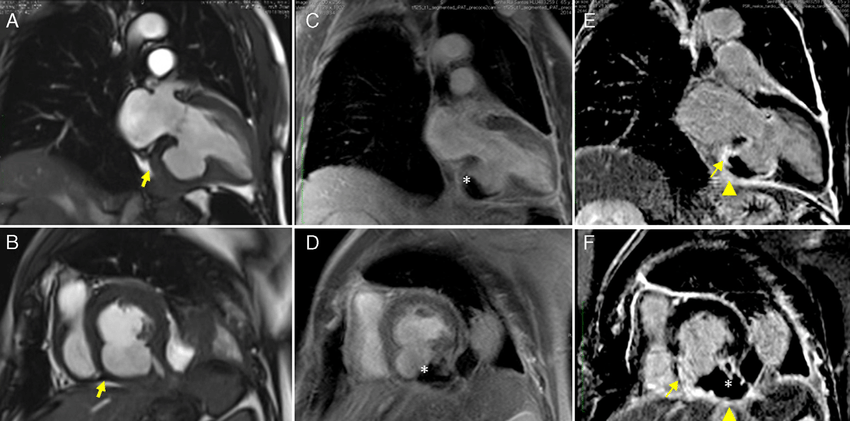

A ressonância magnética cardíaca (RMC) é um exame de diagnóstico por imagem seguro, não invasivo e indolor utilizado para detectar, diagnosticar e monitorar diversas alterações e doenças cardiovasculares. Vamos explorar mais sobre esse exame:

o A RMC produz imagens anatômicas detalhadas da estrutura cardíaca, da função ventricular, da perfusão miocárdica e da caracterização tecidual em diversos planos, incluindo imagens tridimensionais (3D). o É um exame não utiliza radiação ionizante e é usado para avaliar diversas condições cardíacas, como cardiopatias congênitas, doenças da aorta, vasos pulmonares e muito mais. o As imagens são geradas por uma máquina altamente tecnológica, que possui um formato cilíndrico e usa um grande ímã que interage com o corpo do paciente através de um poderoso campo magnético e ondas de radiofrequência.